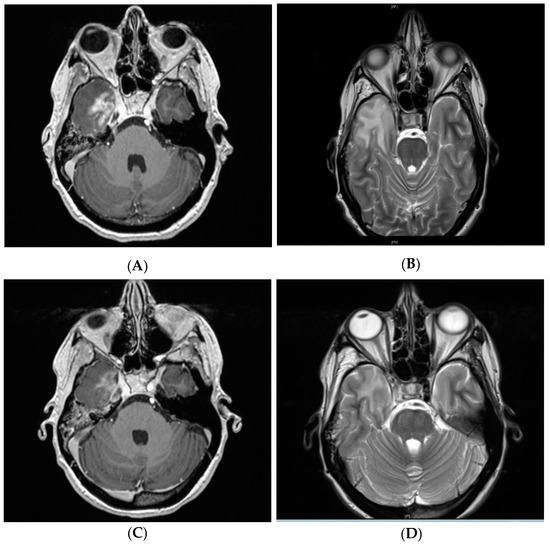

2.2. CNS Necrosis

2.3. Clinical Management and Radiographic Response

- Xu, Y.; Rong, X.; Hu, W.; Huang, X.; Li, Y.; Zheng, D.; Cai, Z.; Zuo, Z.; Tang, Y. Bevacizumab monotherapy reduces radiation-induced brain necrosis in nasopharyngeal carcinoma patients: A randomized controlled trial. Int. J. Radiat. Oncol. Biol. Phys. 2018, 101, 1087–1095. [Google Scholar] [CrossRef]

- Yonezawa, S.; Miwa, K.; Shinoda, J.; Nomura, Y.; Asano, Y.; Nakayama, N.; Ohe, N.; Yano, H.; Iwama, T. Bevacizumab treatment leads to observable morphological and metabolic changes in brain radiation necrosis. J. Neuro-Oncol. 2014, 119, 101–109. [Google Scholar] [CrossRef] [PubMed]